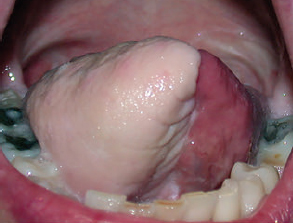

CHAPTER The oral cavity consists of the following structures: the lips, buccal mucosa, mandibular and maxillary alveolar ridge, retromolar trigone, hard palate, floor of the mouth, and anterior (oral or mobile) tongue. The pharynx is anatomically divided into the oropharynx, nasopharynx, and hypopharynx. The oropharynx is bounded by the nasopharynx superiorly, the oral cavity anteriorly, and the hypopharynx and larynx inferiorly. The main structures in the oropharynx are the base of tongue, tonsillar pillars, lateral and posterior oropharyngeal walls, and soft palate. The hypopharynx extends from the level of the hyoid bone to the lower border of the cricoid cartilage, which is congruous with the cervical esophagus below. This is a critical area that is responsible for airway protection and swallowing and speech functions. Common malignancies in the oral and pharyngeal regions include those of the lip, buccal area, floor of mouth, tongue, tonsils, hypopharynx, and larynx. The treatment of these lesions often results in surgical defects that can significantly affect the appearance and function of these vital structures. Providing basic tissue coverage for these defects without considering the functional and aesthetic outcomes is no longer acceptable in modern-day practice. Unfavorable outcomes are common in these complex reconstructions. Proper reconstruction of such defects may prevent life-threatening complications, restore essential functions such as swallowing and speech, and improve patients’ quality of life and self-image. Major head and neck surgery and free flap reconstruction pose significant perioperative risks for patients. Medical complications, not surgical complications, have been proven responsible for slow recovery, prolonged hospital stay, and poor outcomes.1 A thorough medical evaluation and consultation to the medical services before surgery are often required. Many head and neck cancer patients have a long history of tobacco and alcohol abuse. Pulmonary function should be evaluated in those with chronic obstructive pulmonary disease, and cardiovascular workup should be performed as indicated. Preoperative optimization of heart and lung functions is essential to reduce perioperative mobility and mortality. A history of peripheral vascular disease and carotid artery disease has a great impact on the flap selection, recipient vessel selection, and risks for perioperative cerebrovascular accidents. Carotid artery diseases can also be identified on head and neck CT images, which may demonstrate calcification and stenosis. Vascular specialists should be consulted when significant peripheral vascular diseases and carotid stenosis are present. Diabetes is also prevalent in this patient population and increases the risk of surgical site infection. Proper glucose control is essential. Summary Box Complications After Glossectomy and Pharyngoesophageal Reconstruction Choice of flaps is extremely important for oral and pharyngeal reconstruction. Specific defects require several considerations: • Specific flaps with appropriate thickness • Pedicle length • Ability to carry both skin and muscle • Possibility of two skin islands • Skin color match • Donor site morbidity The thickness of the flap affects not only postoperative function, but aesthetic outcomes as well. The paucity of recipient vessels may demand a flap with a long vascular pedicle to obviate vein grafting in an already-complex setting. Therefore, depending on the defects, surgical goals, and availability of recipient vessels, the choice of flap should be carefully evaluated in the preoperative planning session. The patient and family should be made fully aware of potential functional deficits, including the possibility of long-term tube feeding and tracheostomy dependency. Common donor sites such as the forearm, anterolateral thigh (ALT), abdomen, and anterior chest should be evaluated for skin quality and thickness, history of surgery or trauma, and vascular disease. Hand dominance should also be documented. A bracelet with the words “NO IV” is placed on the potential donor site arm, typically the one with the nondominant hand. Defects in the floor of mouth may vary from a small mucosal defect to a large defect involving the musculature with exposed bone. The latter often require postoperative radiotherapy, which significantly influences the methods of reconstruction. Isolated floor-of-mouth defects that do not include the suprahyoid musculature may be skin grafted or reconstructed with a facial artery musculomucosal (FAMM) flap.2,3 However, ligating and dividing the facial artery is common practice during a neck dissection. Therefore reconstruction using the FAMM flap may not be possible for patients who have had a neck dissection. When the floor-of-mouth defect extends to the upper neck, with resection of part of the suprahyoid musculature and exposure of the mandible, more extensive flap reconstruction is indicated. In high-risk patients, the pectoralis major flap is a viable option to fill the dead space in the floor of the mouth and upper neck. In young and more functional patients, however, a free flap is preferred to minimize neck deformity and maximize function. Fig. 51.1 A forearm flap can provide a thin and pliable skin for floor-of-mouth reconstruction that allows full mobility of the tongue. Fig. 51.2 When there is a large soft tissue defect in the floor of mouth, an anterolateral thigh flap with a segment of vastus lateralis muscle can provide reliable coverage and dead space filling. Fig. 51.3 (a) A bulky flap in the floor of mouth can interfere with tongue and lip function. (b) Flap thinning is possible with suction-assisted lipectomy and direct excision at the end of debulking. (c) One year later. The common problems after this type of reconstruction may include a bulky flap that limits tongue mobility and function or inadequate filling of dead space causing infection, fistula, and subsequent bone exposure that may delay adjuvant therapy and cause osteoradionecrosis. The goals are to effectively obliterate the dead space and protect the mandible from postoperative radiotherapy without unwanted bulk that may impede tongue mobility and oral function. A radial forearm flap or ulnar artery perforator (UAP) flap is ideal because they provide a thin and supple lining (Fig. 51.1). A thin ALT flap can also be used to reconstruct the floor of the mouth, with a segment of the vastus lateralis muscle used to fill the dead space (Fig. 51.2). This flap is particularly useful for large defects involving the entire suprahyoid musculature, especially after previous radiation. A shallow floor-of-mouth defect should not be covered with a bulky flap, because it may restrict tongue mobility and obliterate the lingual sulcus, causing drooling (Fig. 51.3). When the resection involves the mandibular gingiva and labial mucosa up to the vermilion border, a common mistake is to suture the flap all the way to the vermilion. This will push the lip downward and completely obliterate the labial sulcus, causing drooling, oral incompetence, and inability to eat and drink. Therefore the flap edge should be sutured to the labial tissue at the base of the labial sulcus. The remaining labial mucosal defect can be left to remucosalize or can be skin grafted. The remucosalization process takes approximately 1 week. The same principle applies to mandibular reconstruction with a fibular osteocutaneous flap when the labial mucosa defect extends to the vermilion (Fig. 51.4). Floor-of-mouth defects commonly involve the ventral tongue. A common practice is to close the tongue to itself by folding the lateral edges of the tongue ventrally and to reconstruct the floor of the mouth with a flap. This technique creates a small “snake tongue” (see Fig. 51.3a) that often causes impairment of speech and swallowing functions. A better approach is to resurface the ventral tongue and the floor of the mouth simultaneously with a thin forearm flap (Fig. 51.5) to preserve the bulk and mobility of the tongue. The tongue is a highly functional organ. A common problem after partial tongue reconstruction is the tethering of the remaining tongue, limiting tongue mobility and function. The most important goal for partial or hemiglossectomy reconstruction is, therefore, to preserve the remaining tongue function. Small defects of up to one quarter or even one third of the tongue, with minimal resection of the floor of the mouth and no communication to the neck, may be closed primarily or with a skin graft (Fig. 51.6). Resection of the floor of the mouth combined with a neck dissection creates a connection between the oral cavity and the neck along the lingual cortex of the mandible. These defects are best reconstructed with a flap to eliminate the dead space, minimizing the risk of infection and fistula formation. The remaining tongue has the ability to move intelligibly as long as it is not tethered. A bulky flap will push the remaining tongue to the side and obstruct its mobility. Therefore a thin and pliable flap should be chosen. The radial forearm flap or UAP flap is usually the first choice. Some adipose tissue in the upper forearm may be included to obliterate the submandibular dead space (Fig. 51.7). A thin ALT flap with a strip of the vastus lateralis muscle can be a good option as well. Fig. 51.4 (a) When resection of labial mucosa approaches the vermilion border, suturing the flap to the mucosal margin may obliterate the labial sulcus and push the lower lip down, causing drooling. (b) A better approach is to inset the flap to the bottom of the labial sulcus and leave the raw surface on the lip to remucosalize. This will preserve the labial sulcus and prevent drooling. Fig. 51.5 (a) After resection of the ventral tongue, closure of the remaining mobile tongue to itself may result in a “snake tongue,” with significant volume loss. (b) An alternative approach to reconstructing the ventral tongue defect is to use a thin forearm flap, part of which is also used to reconstruct the floor of the mouth. To avoid tethering of the remaining tongue, careful flap insetting is important. The length of the ventral tongue, defined as the distance from the tip of tongue to its junction with the floor of mouth and gingiva, is approximately 5 to 6 cm. The distal end of the flap is oriented toward the tip of the remaining tongue. The distal flap width, usually 6 cm, matches the ventral tongue length (Fig. 51.8). Thus one corner of the distal flap is sutured to the tip of tongue, and the other corner to the gingiva. The rest of the flap is sutured to the dorsal tongue medially and gingiva laterally. Such insetting re-creates a nice ventral sulcus and lateral gutter (Fig. 51.9). When there is no gingiva left to attach the flap to, it can be sewn to the teeth by tying the suture knots around the teeth. A single layer of interrupted 3–0 Vicryl sutures usually suffices, although some surgeons prefer horizontal mattress sutures. It is important, however, not to tie the horizontal mattress sutures too tight, which may lead to flap–mucosa edge necrosis and fistula formation. Fig. 51.6 For partial tongue defects without bone exposure or communication to the neck, full-thickness skin grafts can provide excellent coverage with preservation of tongue mobility. Fig. 51.7 (a) Partial glossectomy with neck dissection often leaves a submandibular or upper neck dead space. A conventional radial forearm flap may not have extra tissue to obliterate the dead space. (b,c) A portion of the adipofascial tissue from the upper forearm based on a proximal perforator can be included in the radial forearm for this purpose. Fig. 51.8 For hemiglossectomy reconstruction, the goal is to preserve the remaining tongue mobility without tethering. Adequate ventral sulcus and lateral gutter should be re-created with a 6 to 7 cm wide flap. The distal width of the radial forearm flap is used to re-create the ventral sulcus of the mobile tongue to prevent tethering. Fig. 51.9 With proper flap insetting, the ventral sulcus and lateral gutter of the tongue can be re-created to achieve tongue mobility. Sensory reinnervation can improve swallowing function and patient satisfaction. This can be achieved by coapting the sensory nerve of the flap to the divided lingual nerve. Sensory recovery of the flap with this technique has been well documented. The radial forearm flap, UAP flap, ALT flap, and lateral arm flap can all potentially provide sensory reinnervation.4–9 Unlike hemiglossectomy, a total or subtotal glossectomy leaves no meaningful tongue muscle. Functional outcomes are poor, and aspiration can be a serious complication necessitating a total laryngectomy in some patients. Common problems after total and subtotal glossectomy reconstruction include inadequate bulk resulting in a “funnel tongue,” inadequate vascularized tissue filling resulting in infection and fistula formation, and risks of aspiration related to resection of all floor-of-mouth musculature (Fig. 51.10). The goal of reconstruction is to create enough bulk for the neotongue. Tissue bulk is important for reconstructing large defects of the tongue for two reasons. First, it is needed to help the neotongue touch the palate to produce better speech and push food toward the hypopharynx. Second, the tissue bulk diverts saliva and food to the lateral gutters during swallowing to minimize aspiration.10 With these goals, a bulky flap should be chosen. Some muscle is also needed to obliterate the dead space in the floor of mouth and upper neck. This makes the ALT flap the ideal choice. It also has the advantages of providing sensory and motor reinnervation (Fig. 51.11). The rectus abdominis myocutaneous (RAM) is another good option. Obese men often have more adipose tissue in the abdomen than in the thighs. The opposite may be true for women. It has been suggested by some surgeons to remove the thick cutaneous portion of the flap and use the muscle only. Muscle flaps with or without skin grafts are, however, prone to atrophy and will lose significant bulk, especially after radiotherapy, resulting in a funnel shape that allows food to pour into the hypopharynx and larynx, causing aspiration. A forearm flap is usually too thin for total or subtotal glossectomy defects. Fig. 51.10 A total glossectomy with resection of all floor-of-mouth musculature leaves no tongue muscle to function and increases the risk of aspiration because of the drop of the larynx. Fig. 51.11 Both sensory and motor reinnervation is possible with the anterolateral thigh flap with a segment of the vastus lateralis muscle for total glossectomy reconstruction. (a) The lingua nerve is used for sensory reinnervation. (b) The hypoglossal nerve is used for motor reinnervation. During flap insetting, a dome of neotongue is created so that it can touch the palate easily (Fig. 51.12). Flap insetting can be difficult in a narrow jaw, particularly when no mandibular gingiva is left. It is helpful to inset the flap before revascularization while the flap is still “empty.” In addition to a funnel tongue, drop of the larynx can cause aspiration, which often occurs during a total glossectomy because the suprahyoid musculature is removed. The risk can be reduced with laryngeal suspension. Laryngeal suspension is often performed with circumhyoid sutures (0–0 Prolene) placed through drill holes in the mentum on both sides of the midline.11 The distance between the hyoid bone and the mentum is approximately 4.5 to 5 cm (Fig. 51.13). Care should be taken to avoid compression of the vascular pedicle by these suspension sutures. Fig. 51.12 Volume is necessary for total glossectomy reconstruction to reduce the risk of aspiration and improve swallowing and speech functions. Functional muscle transfer has been successfully used to restore upper extremity functions and for facial reanimation. However, it is rarely used in tongue reconstruction and produces uncertain results. My experience and that of others12,13 have shown minimal muscle movements after a functional muscle flap such as a gracilis flap or ALT flap with the vastus lateralis muscle by coapting the motor nerve of the flap to the hypoglossal nerve. My current approach is to use the ALT flap with vastus lateralis muscle with both sensory and motor reinnervation, because these additional procedures are easy to perform and add little extra time. Without postoperative radiotherapy, reinnervation of the muscle may prevent muscle atrophy. Postoperative radiotherapy, however, may destroy the motor end plates before reinnervation occurs. As with partial glossectomy reconstruction, sensory reinnervation may improve swallowing functions and patient satisfaction.8 Fig. 51.13 After a total glossectomy, static laryngeal elevation can be achieved with circumhyoid sutures to suspend the larynx to the mandible. The difficulties of postlaryngopharyngectomy reconstruction are mainly the results of previous radiotherapy and neck surgery. This increases the risk for delayed wound healing, fistula formation, infection, carotid artery rupture, lack of recipient vessels, a combined pharyngoesophageal and neck skin defect, and tracheoesophageal puncture (TEP) complications. Functional outcomes such as speech and swallowing can be disappointing as well. In addition to being nonvocal after a total laryngopharyngectomy, postreconstruction complications such as pharyngocutaneous fistulas and anastomotic strictures may render patients dependent on tube feeding. Radiotherapy has become the primary treatment for early stages of squamous cell carcinoma in the larynx and hypopharynx. Therefore the majority of laryngopharyngectomy cases are recurrent cancers that have failed radiotherapy and, in some cases, previous neck dissection. These defects are among the most difficult to repair in head and neck reconstruction. The reconstructive goals are to provide alimentary tract continuity, protect great vessels, maximize TEP speech and swallowing functions, reduce the risk of fistula formation, and minimize neck deformity and donor site morbidity. The choice of flaps for pharyngoesophageal reconstruction is important. The flap has a great impact on defect coverage, restoration of speech and swallowing functions, simultaneous neck resurfacing and tracheostoma reconstruction, and donor site morbidity. Commonly used flaps include the ALT flap, jejunal flap, radial forearm flap, and pectoralis major myocutaneous flap.14–20 The pectoralis flap gained popularity in the early 1980s but is used less now because of advances in free flap reconstruction. In general, enteric flaps heal fast but tracheoesophageal (TE) speech is poor and donor site morbidity is higher. Conversely, fasciocutaneous flaps heal slower but TE speech is superior and donor site morbidity is minor.21,22 ALT flaps have largely replaced jejunal and radial forearm flaps in the last decade. If the ALT flap is unavailable because of a lack of perforators or is deemed too bulky, a radial forearm flap or ulnar artery perforator flap is the next choice. In otherwise healthy patients with a circumferential defect, the jejunal flap is another good choice. Contraindications of the jejunal flap include significant comorbid diseases, obesity, and a history of abdominal or gastrointestinal surgeries. The pectoralis major flap can be used for partial defects in male patients, for salvage after failed free flap reconstruction, or in very high-risk patients who cannot tolerate a free flap surgery. The advantage of ALT flaps over forearm flaps is that an ample amount of fascia, the vastus lateralis muscle, and a large second skin paddle can be included for better coverage of the soft tissue defect in the neck, thus potentially reducing the risk of fistula formation. The flap is usually partially inset before revascularization. Recipient vessel choices include the branches of the external carotid artery and facial vein. In a previously radiated and operated neck, using the transverse cervical vessels may avoid difficult and risky dissection around the carotid artery.23,24 Before closure of the neck incision, the neck is slightly flexed with the head in a neutral position. This repositioning may cause kinking or twisting of the vascular pedicle. Therefore the vascular pedicle should be carefully inspected again before closing the neck incision. The second skin paddle is then turned outward to resurface the neck, to reconstruct the tracheal defect, or for flap monitoring. To monitor a buried flap without an external skin island, I prefer externalizing a small skin island based on a second cutaneous perforator or externalizing a small amount of the vastus lateralis muscle based on a muscular branch.25 This technique is highly reliable, because three-dimensional assessment of the entire skin or muscle is possible. This second skin island or muscle is then brought out through the neck incision and covered with petroleum jelly–impregnated gauze to prevent desiccation. A 2–0 silk tie may be placed around the perforator at the skin level so that the pedicle can be easily tied when it is time to remove the monitor segment. The monitor is removed 5 to 7 days later, before the patient is discharged from the hospital. Alternatively, a handheld Doppler device can be used to monitor the perforator or the main vascular pedicle through the neck skin. The Flow Coupler (Synovis) provides an additional method of flap monitoring. With the jejunal flap, a 3 to 4 cm long monitor segment is created from the remaining jejunum based on branches of the pedicle vessels. Both ends of the bowel segment are left open to avoid distention. At the time of neck closure, the tracheostoma is sutured to the surrounding neck and anterior chest skin, and a No. 8 Shiley tracheostomy tube is placed in the tracheostoma and secured to the chest skin. Fig. 51.14 During flap insetting for circumferential pharyngoesophageal reconstruction, positioning the perforators of the anterolateral thigh flap posteriorly may cause perforator compression against the vertebrae and flap failure. Fig. 51.15 The longitudinal seam of the tubed anterolateral thigh flap is positioned more posteriorly with the perforators in the anterior location to avoid compression and kinking. When the ALT flap is tubed to reconstruct a circumferential defect, the perforators need to be carefully positioned. If they are positioned posteriorly against the prevertebral fascia, the swelling of the flap can easily compress the perforators against the hard surface of the vertebrae, causing flap failure (Fig. 51.14). During flap insetting, the proximal anastomosis between the flap and the base of tongue is usually performed first. The longitudinal seam is positioned posterolaterally at the 4 or 8 o’clock position for easy suturing of the T junction. It can be positioned at 6 o’clock if the flap is tubed first. Anastomosis starts with two corner sutures at the 3 and 9 o’clock positions. The posterior wall is then completed, followed by the anterior wall. The tubed flap is slightly twisted so that the longitudinal seam at the distal anastomosis is facing posteriorly at the 6 o’clock position. Such positioning of the tubed flap places the perforator vessels anteriorly between the 11 and 1 o’clock positions to avoid compression of the perforators against the prevertebral fascia. The entire vascular pedicle can be placed anteriorly across the flap to avoid sharp kinking (Fig. 51.15). Anastomotic strictures can result from a circular scar formation, inadequate diameter, a thick flap, postoperative radiation, or fistula. To obtain a sufficient lumen, a flap width of 9.4 cm is required to achieve a 3 cm diameter (3π) for the tubed neopharynx or esophagus.19 For partial defects, the width of the flap is calculated by subtracting the width of the remaining pharyngeal mucosa from 9.4 cm. The flap can be thinned as needed by direct excision of subcutaneous fat at the periphery of the flap. Ample subcutaneous tissue should be left around the cutaneous perforators, and 2 to 3 mm of subcutaneous tissue is left on the dermis to protect the subdermal plexus. The anterior wall of the cervical esophagus is split longitudinally for approximately 1.5 cm to spatulate the distal anastomosis (Fig. 51.16). This is important to enlarge the distal anastomosis and minimize the risk of ring stricture. On the flap side, a triangular lip is created and inserted into the longitudinal split of the esophagus to complete the spatulation (Fig. 51.17). A Montgomery salivary bypass tube with a diameter of 14 mm can be placed inside the tubed flap during circumferential reconstruction in some patients. This technique may further reduce stricture and fistula formation. The indications for the use of the Montgomery tube include a thick flap, difficult flap insetting, very low location of the transected cervical esophageal end, small cervical esophagus, or poor tissue quality because of radiation injury. The tube is inserted through the mouth before the longitudinal seam of the flap is completed. The proximal flange of the bypass tube is placed above the proximal anastomosis, and the distal end is placed in the esophagus below the distal anastomosis. A 1–0 Prolene suture is attached to the flange of the tube, brought out through the mouth, and taped to the cheek to prevent distal migration and facilitate easy removal of the tube. A 10 Fr red rubber catheter is placed over the Prolene suture to protect the oral commissure (Fig. 51.18). Fig. 51.16 To spatulate the distal anastomosis to minimize ring strictures, the anterior cervical esophagus is incised longitudinally for approximately 1.5 cm. Fig. 51.17 A triangular lip of flap is created to be inset to the longitudinal opening of the cervical esophagus to complete the spatulation. Fig. 51.18 For some patients, a Montgomery salivary bypass tube can be placed in the reconstructed esophagus to minimize the risks of leakage and stenosis. (a) A Prolene suture is placed on the flange of the tube and taped to the cheek. (b) A small red rubber catheter is placed over the Prolene suture to prevent the suture cutting through the oral commissure. If a feeding tube has not yet been placed, a Dobbhoff feeding tube is placed through the nose and flap or inside the Montgomery salivary bypass tube, and through the cervical esophagus to the stomach. The Montgomery tube is usually removed 4 to 6 weeks after reconstruction. This can be done in the clinic without sedation by pulling out the previously placed Prolene suture. In my experience, pharyngocutaneous fistulas occur in 6% of patients.19,20 Fistula rates are similar in partial and circumferential reconstructions. Pharyngocutaneous fistulas occur more commonly at the distal anastomosis than at the proximal anastomosis, most likely related to the thin, less well-vascularized cervical esophagus compared with the base of the tongue. In fact, proximal fistulas are rare with the ALT flap unless there is a dehiscence from poor tissue quality. It has been speculated that the longitudinal seam of a tubed fasciocutaneous flap or two longitudinal suture lines in a partial defect might have contributed to a higher incidence of fistula formation with the radial forearm flap. However, in my experience, the fistula rate with the ALT flap is no higher than with the jejunal flap, and no fistulas have occurred through the longitudinal suture lines. Fistulas usually develop between 1 and 4 weeks postoperatively and manifest as leakage of saliva or liquids or, in some patients, as a neck infection. Therefore any neck infection or abscess that occurs after a pharyngoesophageal reconstruction should raise suspicion for anastomotic leakage. Risk factors for fistula formation include improper suturing techniques, poor tissue quality at the anastomosis site, previous radiotherapy, lack of well-vascularized tissue protection of the anastomosis, and turbulent postoperative course. At the time of surgery, any questionable tissue in the proximal pharynx and cervical esophagus should be trimmed until well-vascularized tissue is seen. Although a watertight seal using a horizontal mattress suturing technique is advocated by some, I believe that such tight horizontal mattress suturing may actually cause necrosis of the mucosal edges and thus increase the risk for fistula. I prefer single-layer, simple interrupted 3–0 Vicryl sutures for flap insetting, taking relatively big bites, inverting the skin and mucosal edges into the lumen, spacing each suture 5 to 7 mm apart, and avoiding tight knots. To further protect the suture lines, a second layer of fascial closure is recommended. Fig. 51.19 A novice mistake is to deepithelialize a strip of skin and externalize a portion of the flap for neck coverage. This results in a high fistula rate. Once a leakage occurred in this patient, the de-epithelialized portion reepithelialized quickly because of the lack of contact inhibition, resulting in a nonhealing fistula. During ALT flap harvesting, a wider amount of fascia than skin is included in the flap. When making the anterior incision, the fascial incision is made 1 to 2 cm more medially than the skin incision. Likewise, an additional 1 to 2 cm of fascia is recruited posteriorly. After completion of flap insetting, the extra fascia of the flap is wrapped around the flap to reinforce the suture lines and cover the anastomoses. Placement of the Montgomery salivary bypass tube inside the flap may also reduce the risk of fistula in high-risk patients by protecting the anastomosis from constantly soaking in saliva. If neck resurfacing is needed but only one cutaneous perforator remains, an attempt might be made to externalize a portion of the distal flap by deepithelializing a strip of skin around the distal anastomosis (Fig. 51.19). This, however, results in a high fistula rate.19 Even with a minor leakage, the deepithelialized portion will reepithelialize, causing a nonhealing fistula. The timing for resuming an oral diet after surgery may also have an effect on fistula formation. The radial forearm flap has a reputation of having high fistula rates and having delayed fistulas that occur 4 to 5 weeks after surgery.14,15 A fasciocutaneous flap does not heal as quickly as a jejunal flap once it is immersed in saliva 24 hours a day. This may explain the high incidence of delayed fistula formation. In fact, the anastomosis may experience secondary healing, which could take 4 to 6 weeks. If an oral diet is started early, for instance 7 days after surgery, as with the jejunal flap, fistulas will likely develop with the unhealed fasciocutaneous flap. After fasciocutaneous flap reconstruction, I routinely delay oral intake for 2 weeks in nonirradiated patients and for 4 to 6 weeks in patients who have undergone radiotherapy. Before oral intake, a modified barium swallowing study is performed. If no leaks or fistulas are identified, a liquid diet is started and then advanced to a regular diet as tolerated. In the presence of a leak, oral intake is delayed, and the modified barium swallowing study is repeated in two weeks. Most leaks heal within 2 weeks. In a previously irradiated patient, the tracheostoma is at risk for necrosis and dehiscence. This could be the result of an ischemic tracheostoma itself or ischemic neck and chest skin or tight closure. The blood supply to the trachea arises laterally. Extensive lateral dissection on both sides to skeletonize the trachea should be avoided. When the tracheal stoma is short, excessive undermining of the previously irradiated anterior chest skin to reach a low tracheostoma under tension can easily cause skin necrosis, because it is compressed over the clavicular heads. An alternative approach to mature the anterior wall of the tracheostoma is to use a pedicle internal mammary artery perforator (IMAP) flap.26 Questionable neck skin around the tracheostoma should be débrided, and well-vascularized skin from the flap should be used instead. Full-thickness skin grafting over the vastus lateralis muscle to mature the posterior tracheostoma and anterior neck can provide very stable coverage. Another common problem with the tracheostoma is partial obstruction related to a bulky second skin paddle for external coverage. The skin paddle should be thinned as much as possible at the time of reconstruction. Alternatively, muscle and skin grafting can provide excellent results. When a Shiley tube is placed in the tracheostoma with a bulky skin paddle, the flange of the Shiley tube can cause compression and necrosis of the skin around the tracheostoma. To avoid this, the superior flange of the Shiley tube is trimmed and a longer tube should be used (Fig. 51.20). The flap can also be thinned using suction-assisted lipectomy several months after surgery; this method works extremely well. For tracheoesophageal voice rehabilitation, patients commonly wear a hands-free stoma button. This button needs to sit inside the tracheostoma securely. Ideally, the tracheostoma should have a circumferential flange to secure the voice button without the bowstring of the neighboring sternocleidomastoid (SCM) muscles. This can be achieved by dividing the medial edges of the SCM before neck closure and maturing the tracheostoma using a semivertical mattress suturing technique to create a flange (Fig. 51.21). A frozen or woody neck, defined as severe fibrosis in the neck without tissue planes, is the result of neck surgery (such as neck dissection) combined with radiotherapy.24 Long-standing pharyngocutaneous fistulas usually result in the worst cases of frozen neck. There are three major problems associated with managing a frozen neck during reconstruction: 1. Risk of carotid artery rupture 2. Lack of recipient vessels 3. Concomitant neck skin or tracheal defects